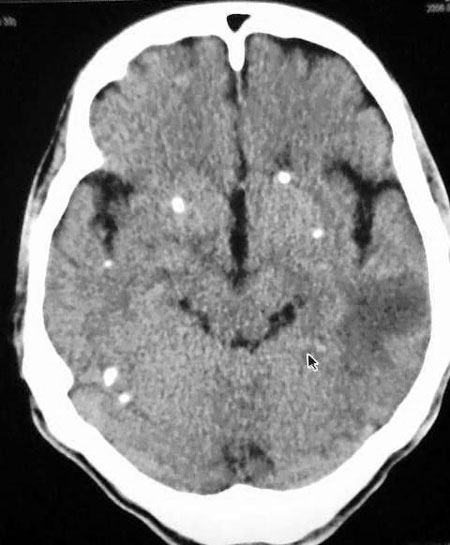

以下是引用守望可可西里在2006-9-6 8:01:00的发言:[br][br] “国内文献进行了脑囊虫病的ct分期:①活动期: ct标志为头节、囊壁、囊液同时存在,分为脑实质小囊型与脑室型;②退变死亡期:ct标志为头节消失、囊腔肿大、虫体崩解,分为单发或多发小囊型、大囊型、葡萄状囊丛型、脑炎型、脑内小脓肿型、脑梗塞型、脑膜炎性③钙化期:标志为囊虫灶转为高密度的钙化结节;④混合期:为活动期、退变期、钙化期病灶混合存在。”[br] 本病例左颞叶、右颞顶叶低密度影,无占位表现,病灶极似脑梗塞。但双侧病灶中偏边缘部位还是有圆形钙化灶,可以考虑为虫体钙化。再加上脑实质内见散在的不对称圆形钙化,其形态类似“大米粒状”,本例应该考虑是脑囊虫病,分期为混合期。